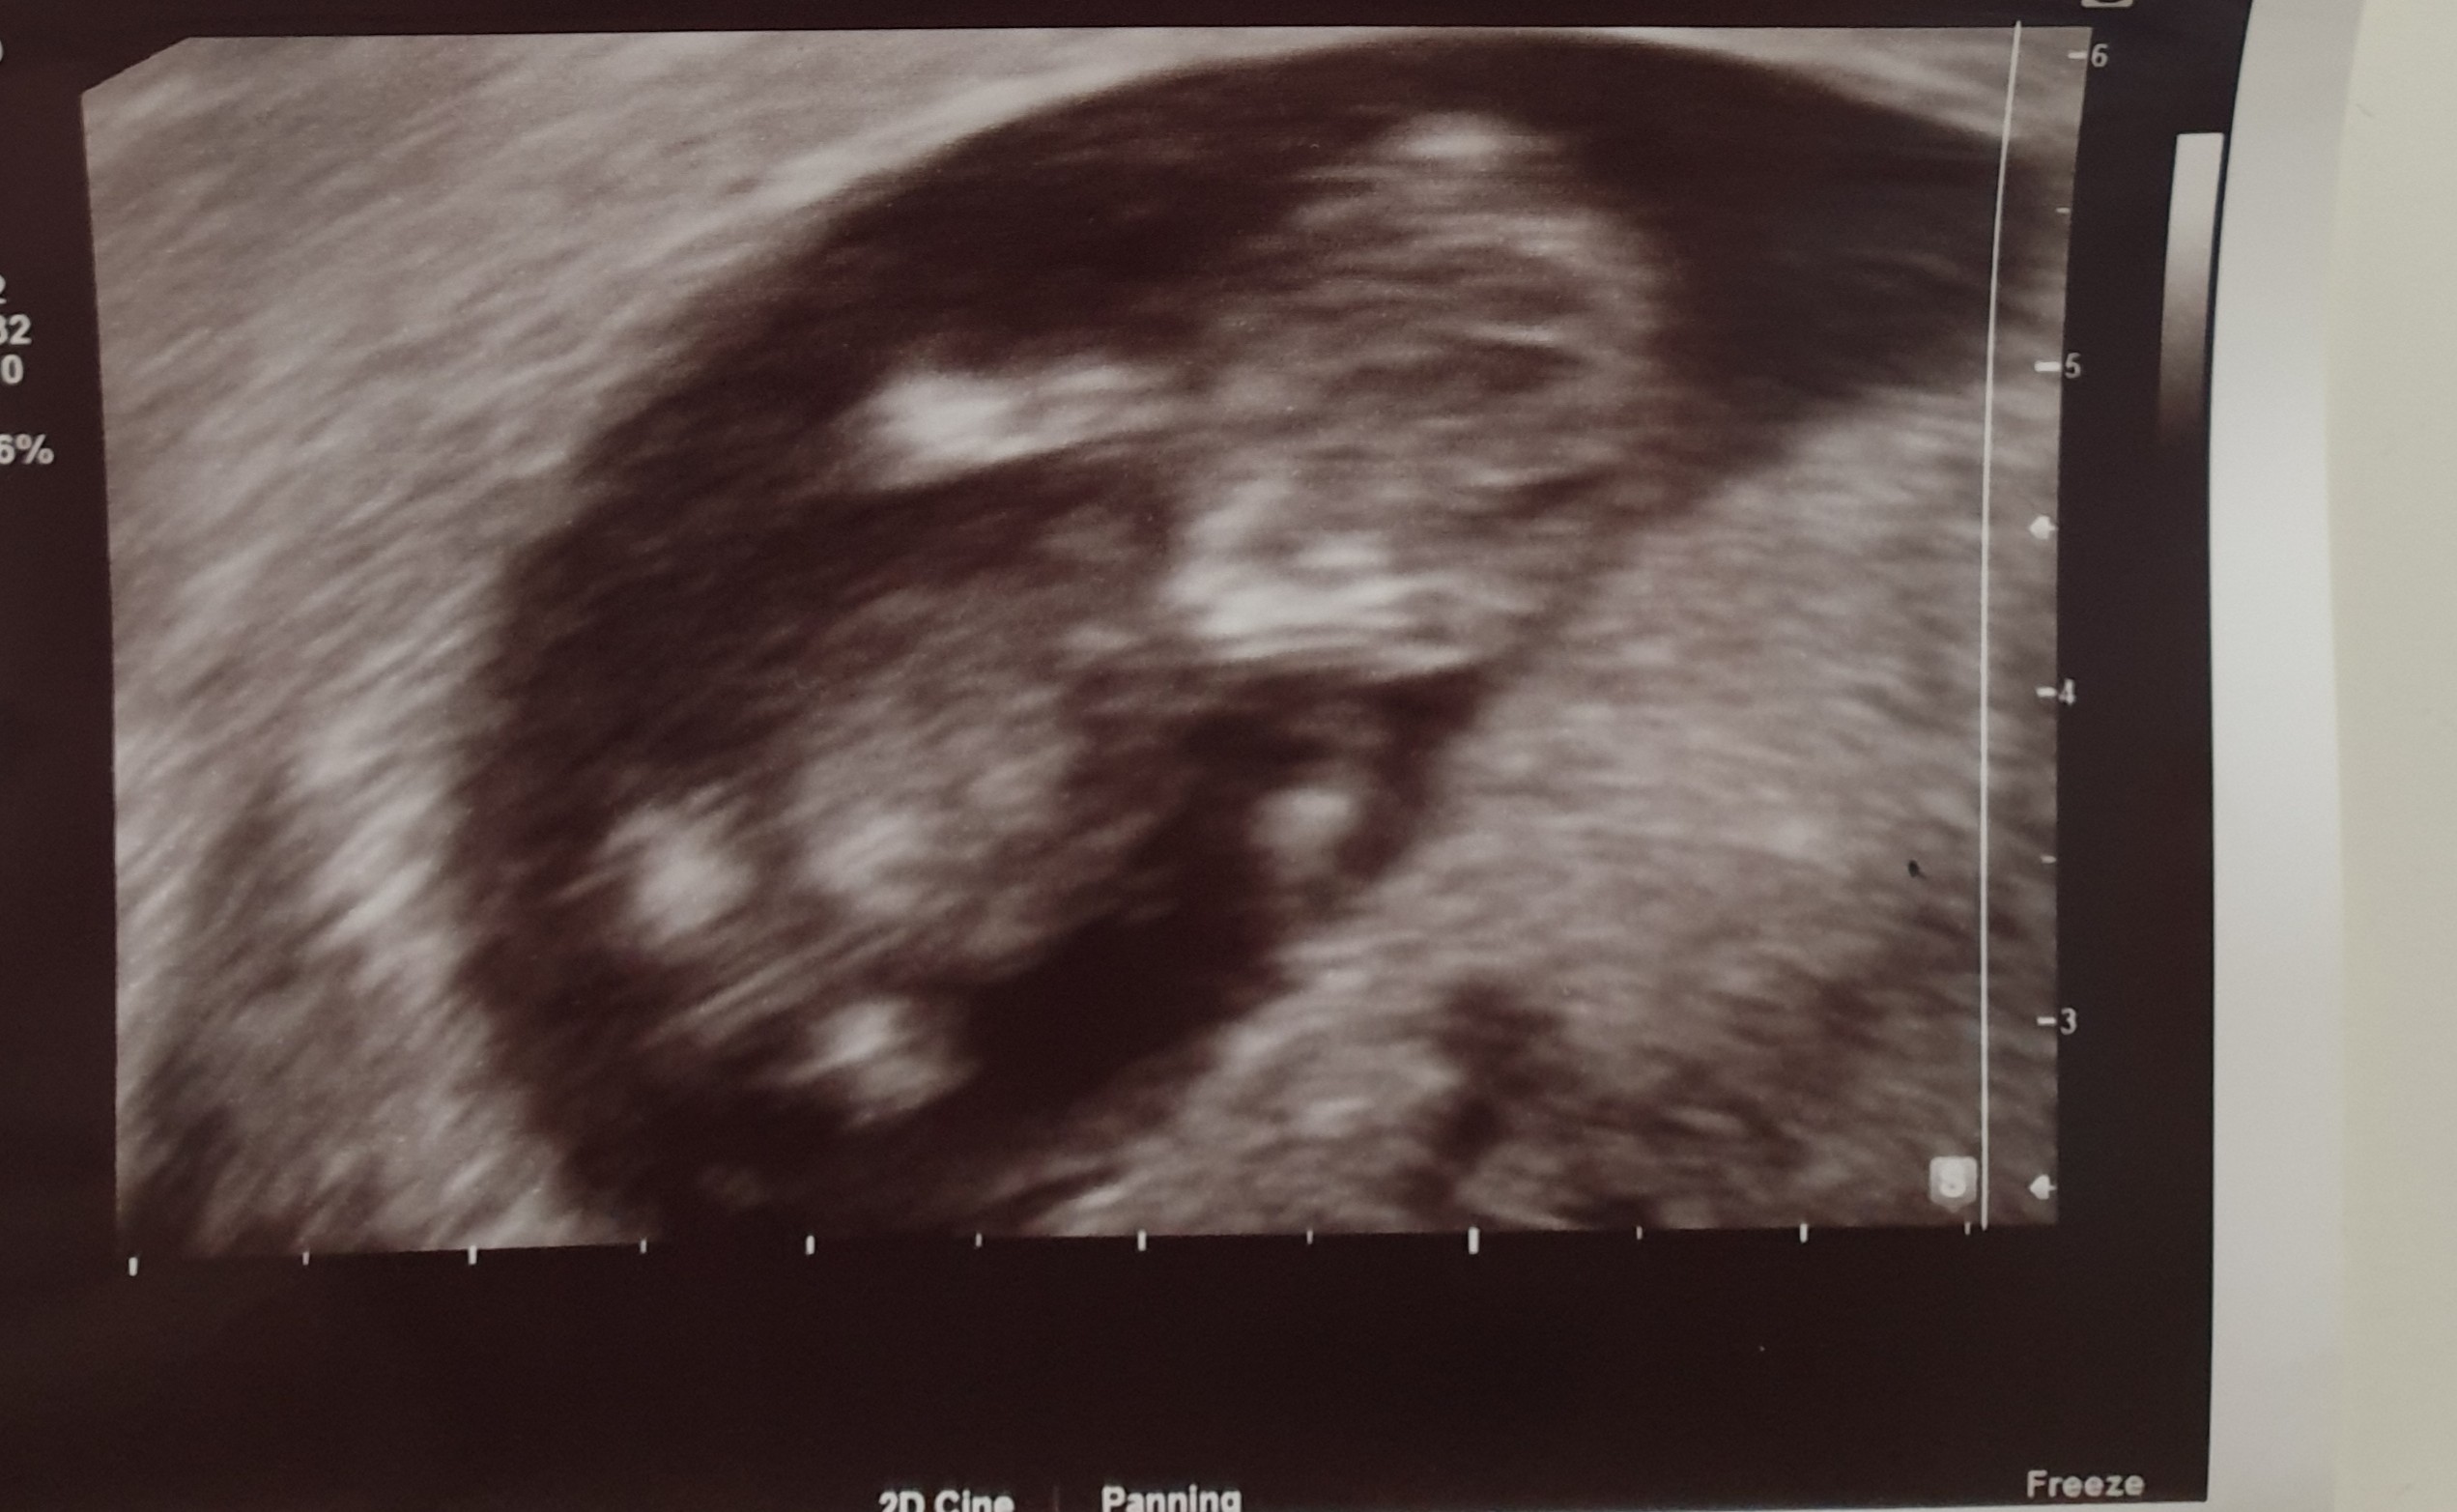

Ja już po wizycie, wszystko dobrze, dzidziuś dalej wypada tak samo z usg jak z ostatniej miesiączki, czyli 10+4 i ma już 3,66 cm. Ładnie się ruszał na usg :) Tylko nie wiadomo skąd to plamienie, także nakaz oszczędzania się i zwiększona dawka duphastonu do końca tygodnia..